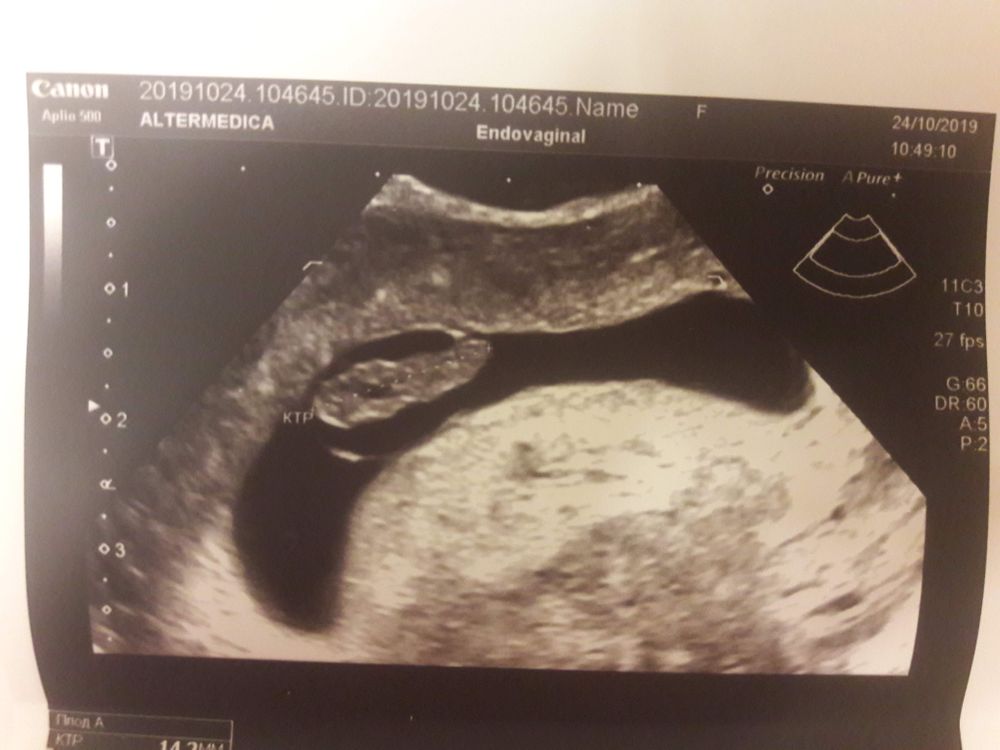

Девочки всем привет , сегодня 6.1 неделька , и у меня маленькая радость нашли моего малыша и услышали сердечко 😍❤️Естественно словами не описать все те чувства которые испытываешь в момент, когда узист говорит " мамочка вам малыш машет ручкой, улыбнитесь" 😍😭КАЖДОЙ на этом свете желаю испытать эти шикарные чувства 🙏😍 Все соответствует сроку тьфу тьфу. Нашли причину моим розовым выделениям , гипертонус матки 😔 Хорошо что я не послушала врача и пошла на УЗИ сегодня , а не 15-17 числа. На данный момент ставлю Вибуркол и Утрожестан уже как неделю . Подскажите пожалуйста , кто что принимал от гипертонуса и даёт ли что то Утрожестан ??🙏